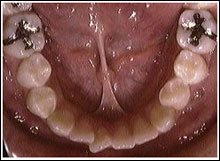

舌小帯と開咬

舌の運動機能障害

症例

永久歯が後ろから!?